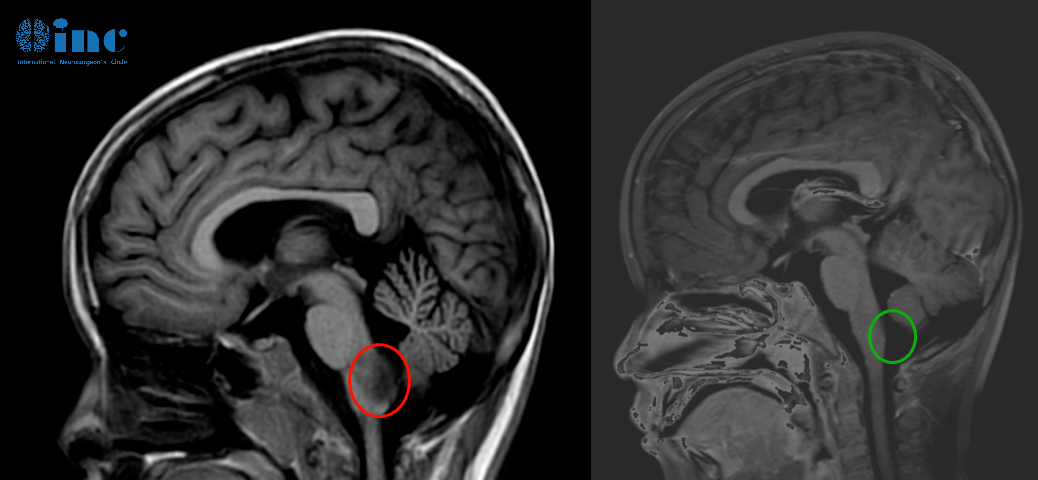

巴教授顺利近全切天天的脑干-延髓毛细胞星形细胞瘤。

▼天天术前术后影像对比图片

术后三天查房交流清晰、肢体抓握能力正常、术后呼吸吞咽正常,食欲正常,已经可以正常吃饭进食。